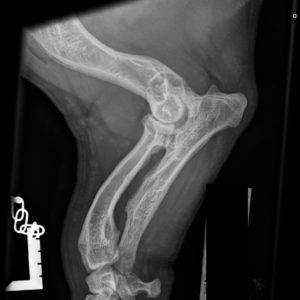

Kyynärnivelen epäyhdenmukaisuus näkyy parhaiten röntgenkuvassa, jossa niveltä ei ole taivutettu (avautumiskulma 90 astetta tai enemmän). Röntgenkuvassa täytyy näkyä kyynärnivelen lisäksi koko kyynärvarsi. Epäyhdenmukaisuus (inkongruenssi) arvioidaan asteikolla INC0 – INC3, jossa INC 0 on yhdenmukainen ja INC3 on voimakkaasti epäyhdenmukainen nivel. Kondrodystrofisilla roduilla INC1 on vielä ”normaali”, mutta INC2- ja INC3-kyynärnivelet ovat selvästi epänormaaleja.

INC0 (normaali): Nivelrako on kapea ja tasainen, kyynär- ja värttinäluun välillä ei ole porrasta. Ei nivelrikkoon viittaavia muutoksia.

INC1 (lievä): Nivelrako ei ole täysin kapea ja tasainen: kyynär- ja värttinäluun välillä on pieni porras tai nivelraossa olka- ja kyynärluun välillä on korkeintaan 2 mm leveä rako. Ei nivelrikkoon viittaavia muutoksia.

INC2 (kohtalainen): Nivelrako ei ole kapea ja tasainen: kyynär- ja värttinäluun välillä on porras tai nivelraossa (incisura trochlearis) olka- ja kyynärluun välillä on 2–3 mm leveä rako.

INC3 (vaikea): Nivelraossa olka- ja kyynärluun välillä 3 mm tai sitä leveämpi rako tai kyynär- ja värttinäluun välillä on porras, tai nivel on muuten selvästi epämuotoinen